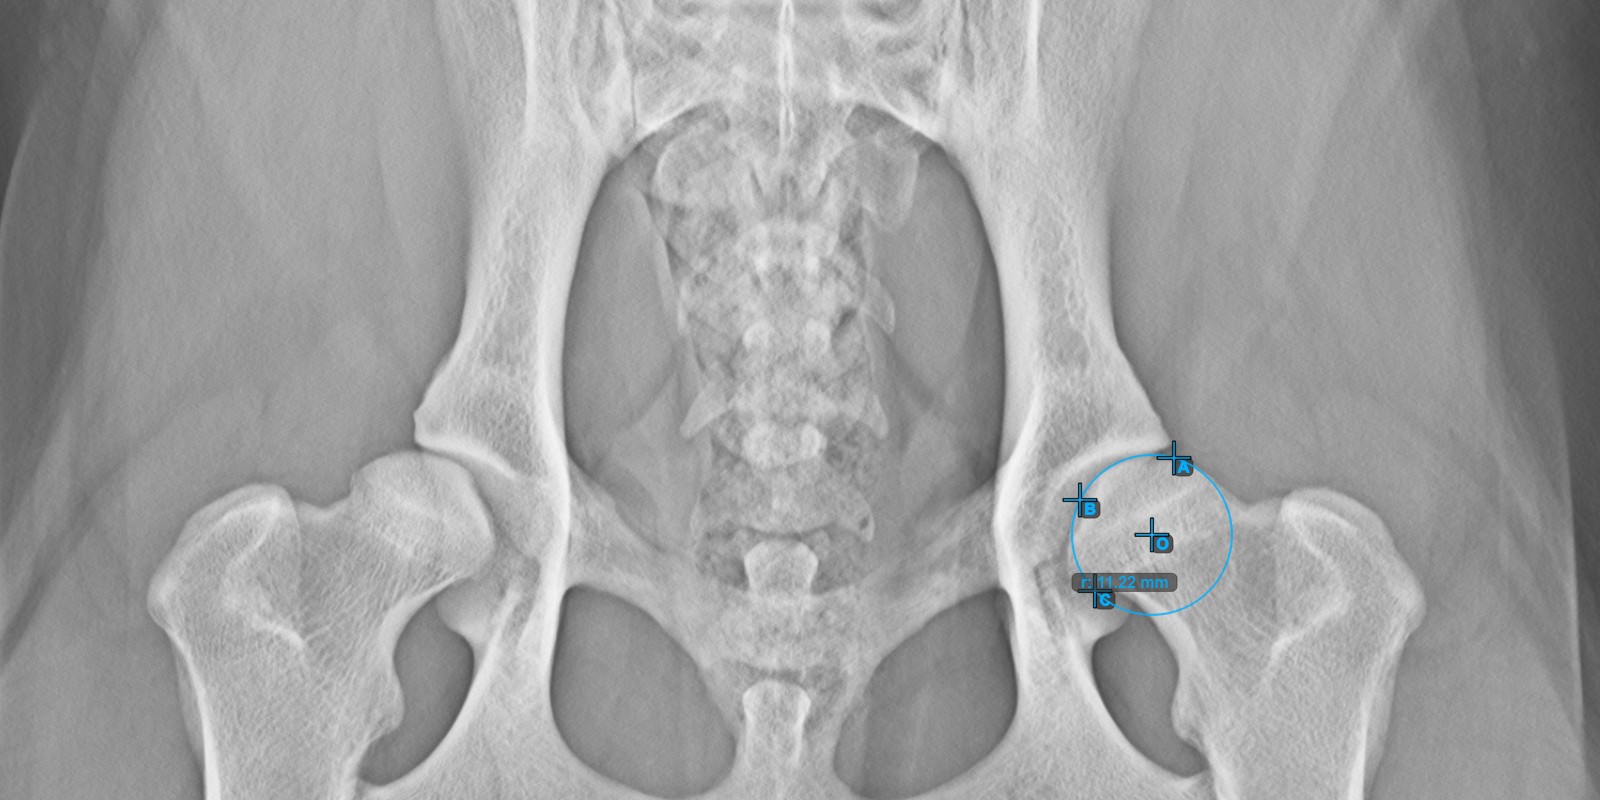

Calculate the right Norberg Angle measurement by marking a line on the effective edge of the right Acetabularis bone, completing the entire advanced measurement.

Mark a point near the right Caput Femoris and drag it along the effective edge of the right Acetabularis bone, forming the terminal side of the right Norberg Angle.

The drawn line must be a tangent to the effective edge of the right Acetabularis bone. The value and arc of the angle is automatically calculated.

The image below depicts the typical placement of the line and the calculated Norberg Angle measurement.